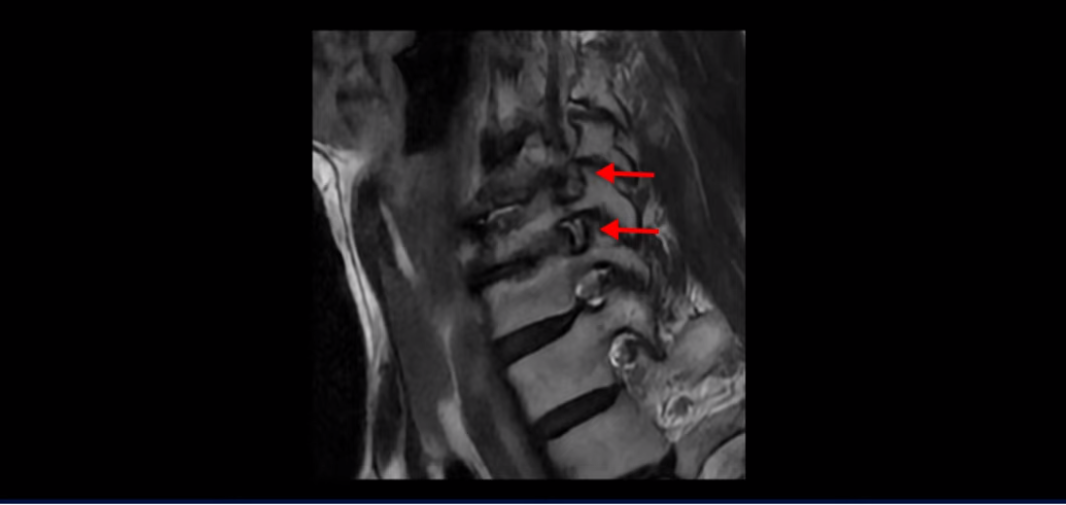

먼저 이분 MRI와 X-ray 보면서 간단히 설명해 드린 후 어떻게 목 협착증으로 신경이 눌려서 극심한 목통증과 견갑골 통증이 몇 달씩 지속되고, 고개가 조금도 돌아가지 않고 하루 24시간 아파서 잠도 잘 수 없는 환자가 수술 없이 비수술 치료로 좋아질 수 있는지, 치료는 어떻게 하는지 자세히 설명해 드리겠습니다. 참고로 이 환자분의 치료 후기는 2개입니다. 이분은 허리에도 심한 전방전위와 협착이 있어서 목 치료와 함께 허리 치료도 받으셨고, 허리 치료 후기 영상도 있으니 별도로 보시길 바랍니다.

이분 목 X-ray를 보면 역C자형의 목에 전방전위도 보이고,

두 마디의 디스크가 거의 닳아서 뼈들이 거의 붙어 보입니다.

목도 많이 휘어 보입니다.

MRI를 보면 2마디 디스크의 퇴행이 아주 심해 보입니다.

그래서 오른쪽 신경 가지가 빠져 나가는 추간공 2개와

왼쪽 추간공 두 개가 모두 많이 좁아져 있습니다.

이렇게 신경 구멍들이 좁아져 있고 신경 주사가 효과가 없으니까 동네 정형외과에서는 무조건 대학병원으로 가라고 했는데요. 가서 수술 받으라는 얘기겠죠. 그런데 저희 모커리한방병원은 협착증은 수술 없이 치료가 잘 될 수 있는 질환이라고 계속 설명하고 있는데요. 왜 그럴까요? 저희가 협착증이 왜 수술 없이 치료 가능하다고 설명하는지에 대해 잘 이해하시려면 무증상 협착이라는 개념에 대해 잘 이해하셔야 합니다.